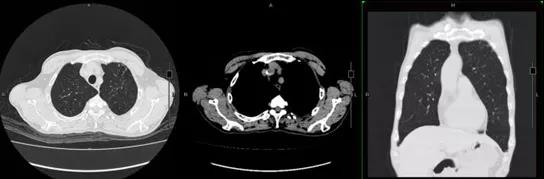

患者1个月前(2018年3月31日)因胸痛至我院就诊,诊断为急性肺动脉血栓栓塞症(图1A),4月8日复查胸部CT示血栓吸收不明显(图1B),遂于4月11日予阿替普酶50 mg溶栓治疗,后予华法林抗凝治疗,4月16日复查胸部CT示血栓吸收,好转后出院(图1C)。

图1 患者胸部CT

注:A为3月31日患者双肺动脉主干及分支多发肺栓塞;B为4月8日患者双下肺动脉干及右中叶动脉栓塞较前稍有吸收;C为4月16日双下肺动脉干及分支栓塞较前吸收